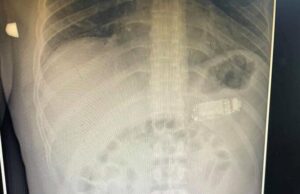

Un deținut s-a plâns de dureri de stomac mai multe zile....

Un chirurg kosovar a scos cu succes un telefon mobil Nokia 3310 din stomacul unui deţinut, în urma unei intervenţii la o clinică din...